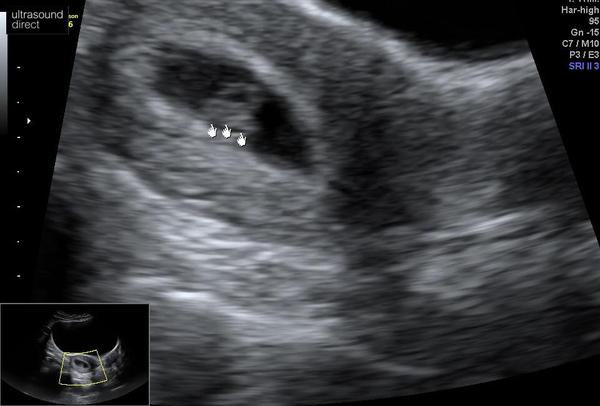

Novella12 · 22/03/2022 18:54

@sarahxdx I had my scan today at 6w 6d! All good and we saw a little heartbeat, it was external too. Good luck for Friday!

@roobearbaby awww look 🥰🥰 congratulations xx